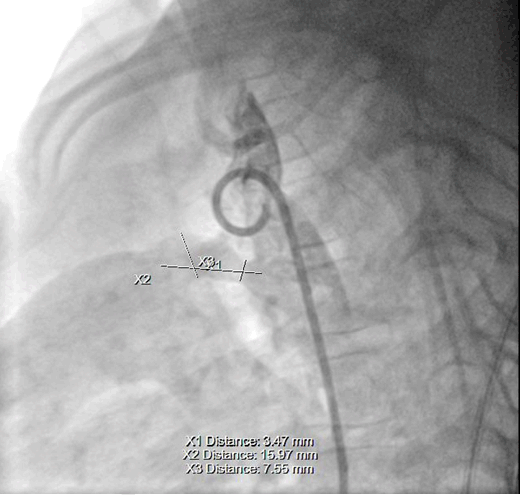

The patient was arranged to have a cardiac catheterization with trial of closure of the PDA if possible, her PDA was type D subtype (complex duct with multiple constrictions) with aortic side is 3.1 mm *midpoint 4.7 *pulmonary end 1.0 mm (Figure 1) but because of unavailability of occluder devices, closure was postponed.

Figure 1: Initial angiographic appearance of the patent ductus arteriosus.